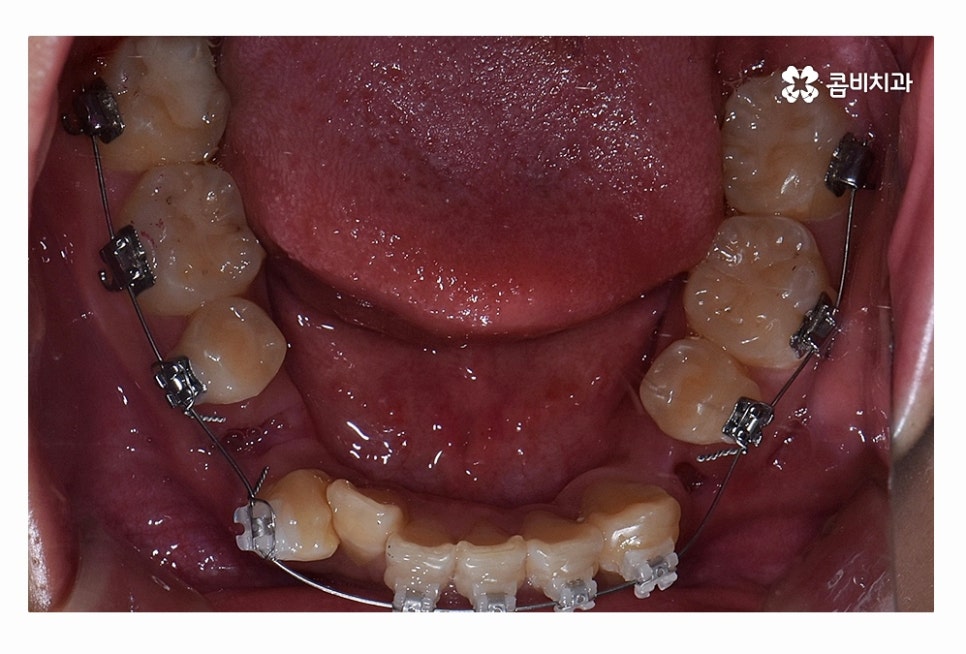

오늘 보시는 환자분의 사례처럼 덧니가 치아끼리 겹쳐 있는 경우에

치아의 이동 공간 확보를 위해서 덧니 발치 필요한 사례였으며

교합과 치아교정 후 얼굴 변화를 고려할 때도 치아교정 과정에서

발치가 필요한 사례였다고 볼 수 있어요.